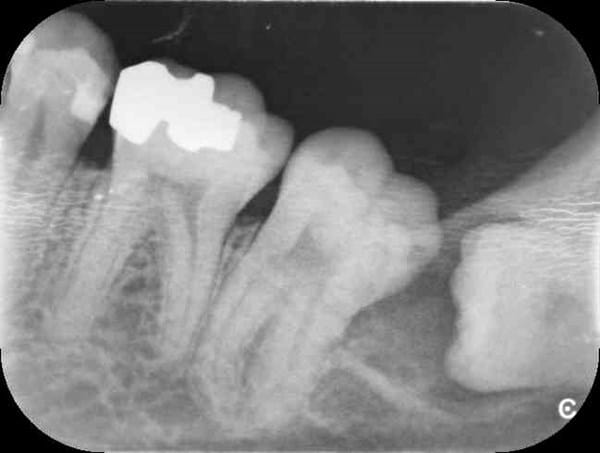

Caries dental tras radiografía boca completa

Me gustaría saber si tengo caries dental en esta radiografía ( En ese diente que esta pegado al cordal), unos dentistas me dicen que si y otros que no . Muchas Gracias . Un saludo.